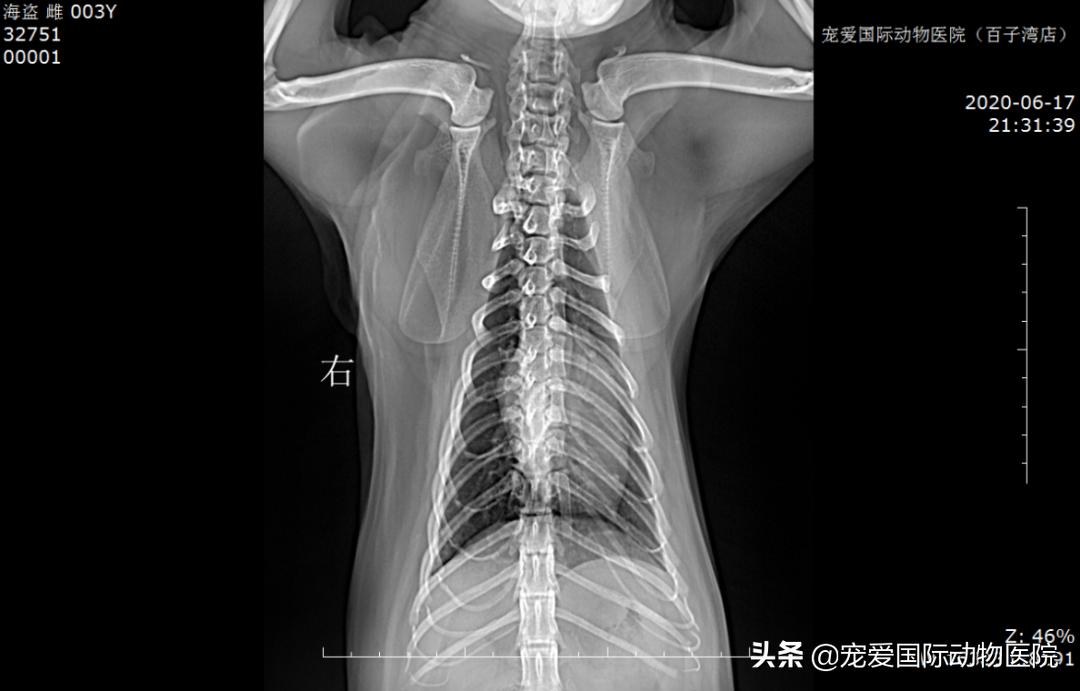

DR显示:

侧位X光片未见明显肺水肿

正位x光提示肺水肿好转

(较转院来时他院结果)